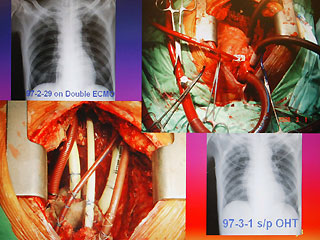

病人陳先生感染細菌性心內膜炎,造成心臟破壞(左下方),進行全心臟摘除術,并放置葉克膜(右上方)體外維生系統以維持生命。

報道說,現年60歲的陳先生,2月初因發現感染細菌性心內膜炎,致使整顆心臟感染嚴重,從奇美醫院轉到臺大醫院之后,經家屬同意,決定進行全心臟摘除,然后置入葉克膜維持生命。陳先生最后靠著葉克膜撐過16天,奇跡式活下來,于今天順利出院。

王水深說,摘除心臟時沒人能保證有心臟可換,而靠葉克膜體外維生系統通常也只能維持7天左右,但陳先生靠著兩套葉克膜奇跡式的撐過16天,克服感染及排斥,又能幸運的等到心臟捐贈者,他強調,翻遍文獻可說史無前例。(周先)